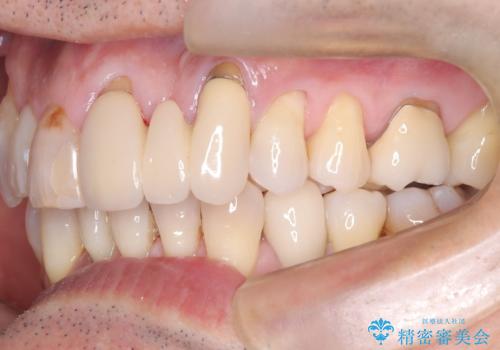

50代からの矯正治療!ブリッジを活かし八重歯を解消

- 50代の患者様で、右上の八重歯と歯並びの乱れを気にされてご来院されました。特に、すでに装着されている前歯のセラミックブリッジを外したくないという強いご希望がありました。精密な検査の結果、八重歯を治すためのスペースが不足しているため、右上の4番目の歯(小臼歯)を抜歯し、そのスペースを利用して歯並び全体を整える治療計画を立案。装置には目立たないインビザラインを採用し、ブリッジを温存しながら八重歯の改善を目指しました。

今回の治療で最も重要だったのは、患者様のご要望通り既存のセラミックブリッジを外さずに矯正を進める点でした。計画通り右上の小臼歯を抜歯し、透明なインビザラインを使用して抜歯スペースを閉じながら、八重歯を正しい位置へ移動させました。ブリッジの形態と調和するに、他の歯の移動を工夫をすることで、複雑な条件をクリア。治療の結果、長年気にされていた八重歯が解消され、見た目が大きく改善しました。50代からでも、ご自身の要望を叶えながら、美しく機能的な歯並びを獲得していただけました。